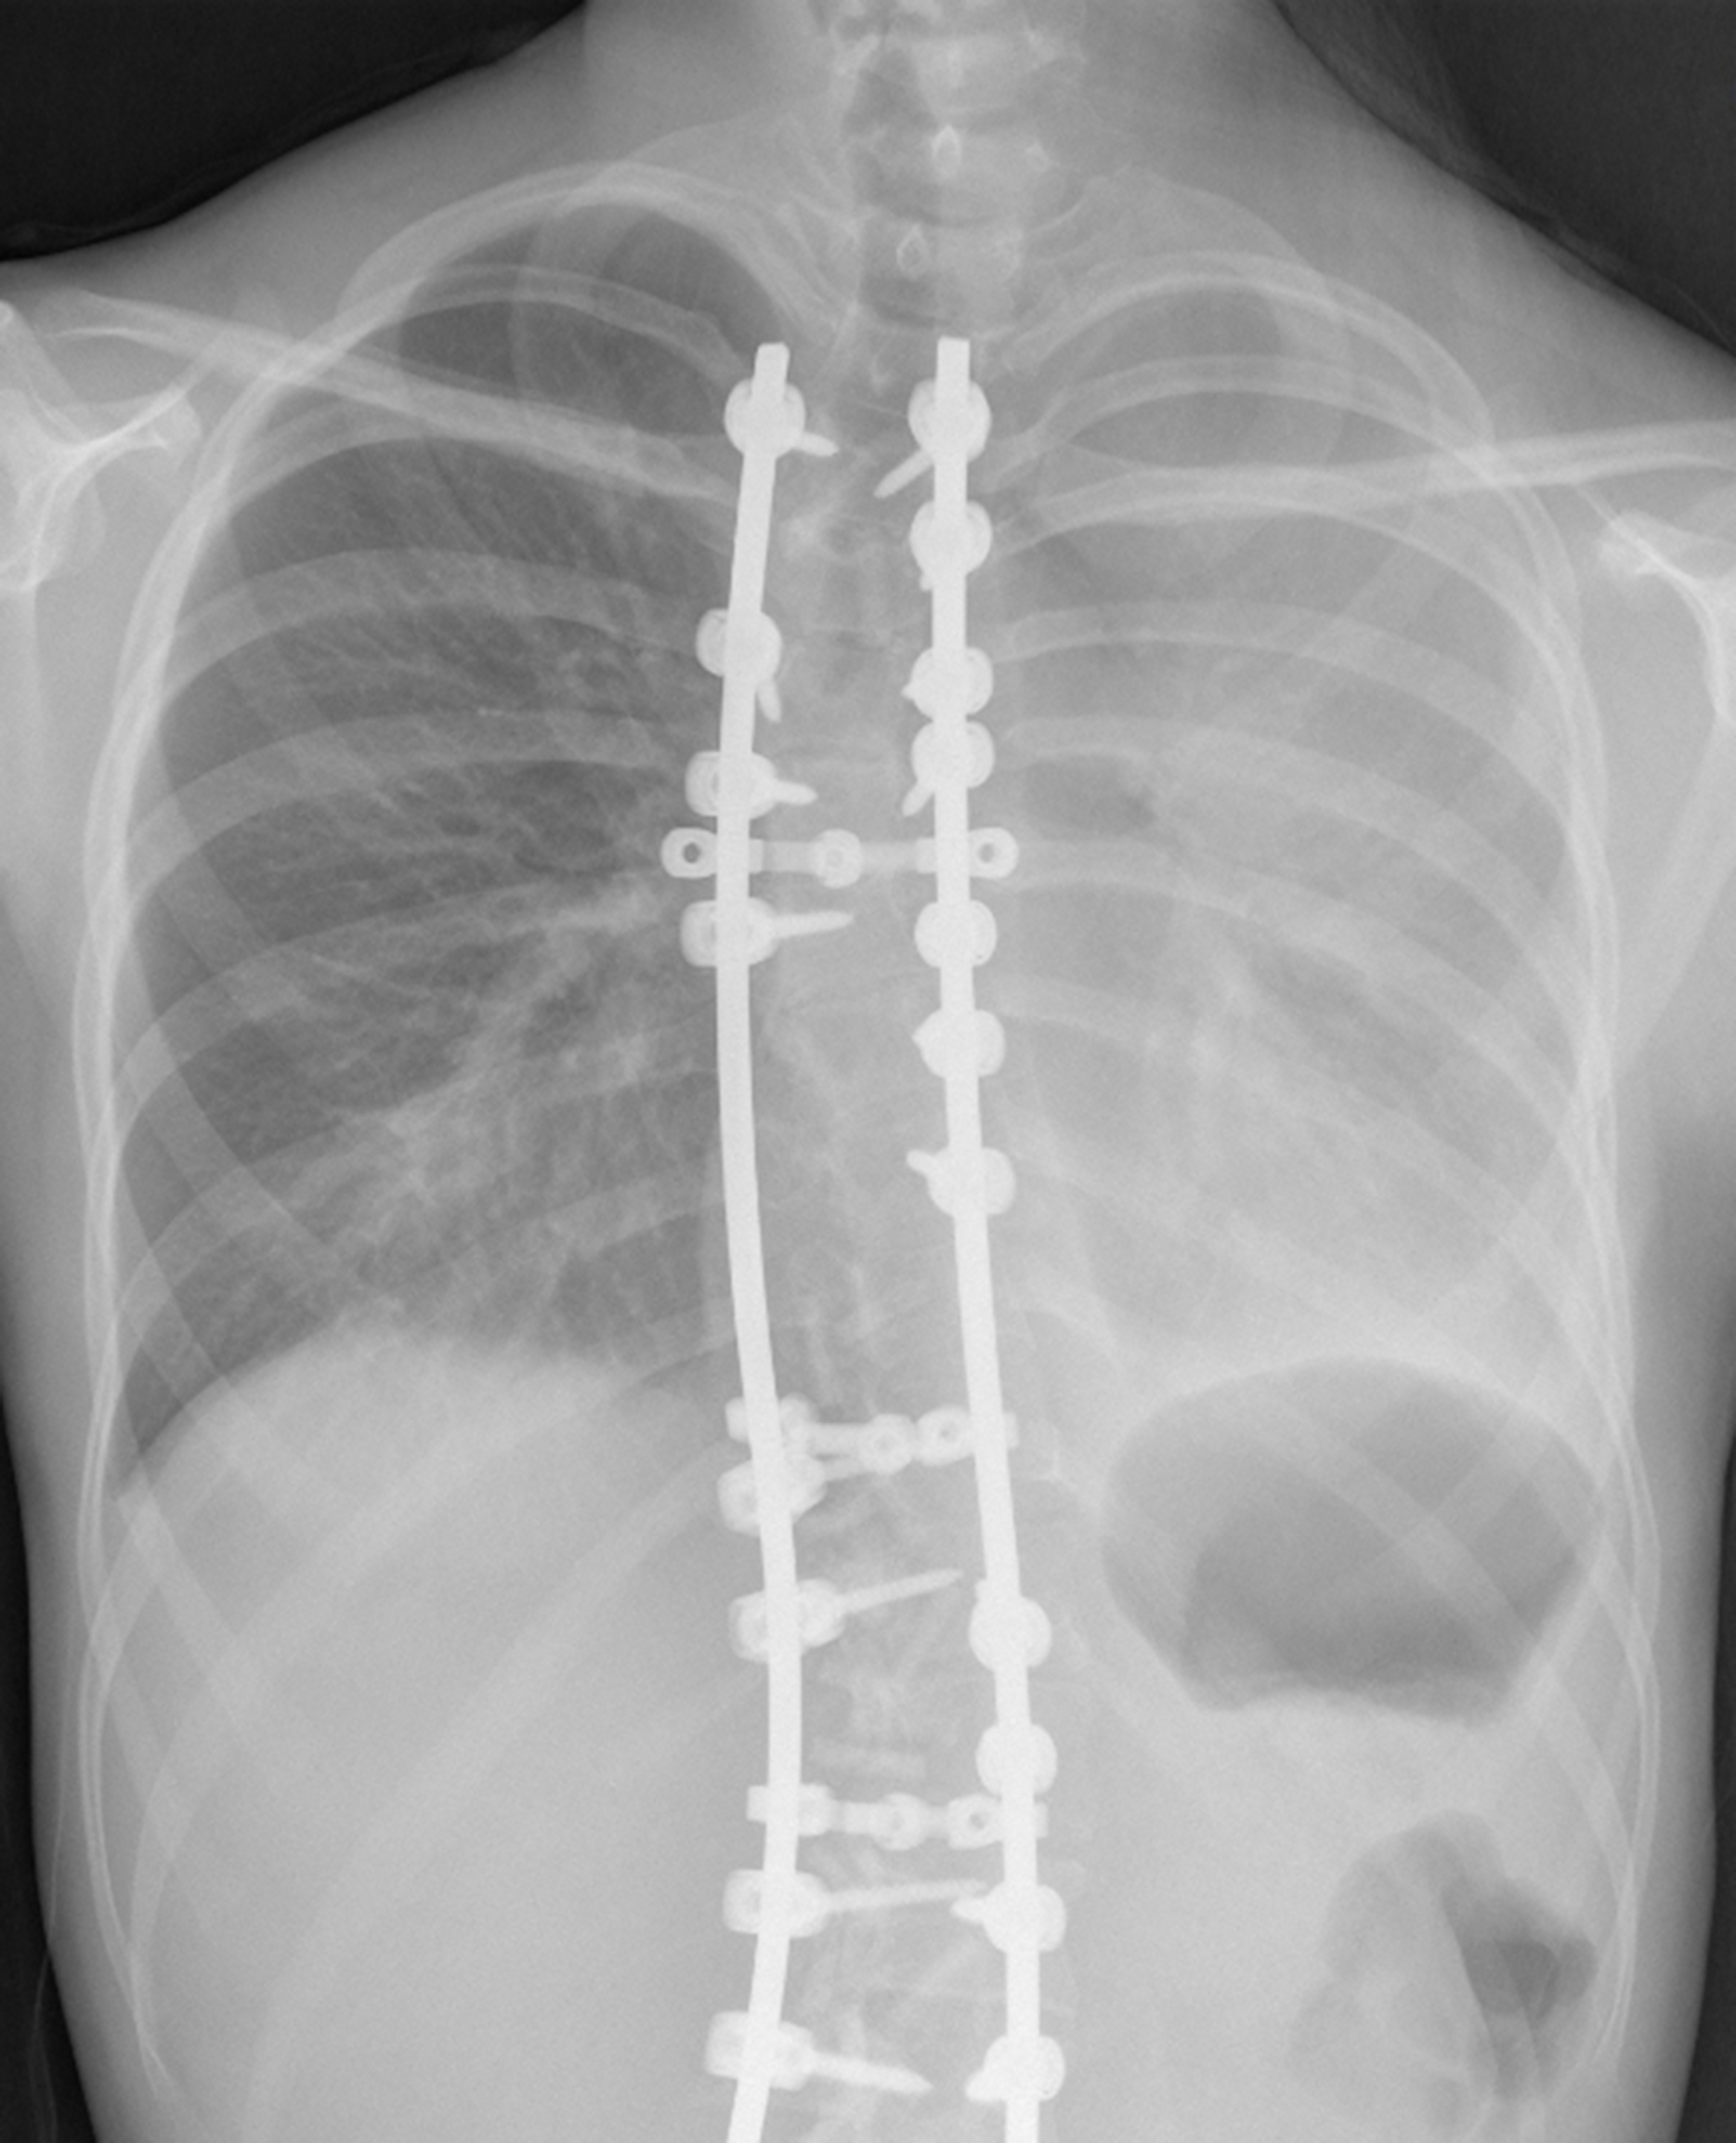

- Figura 2 (Português (Portugal))